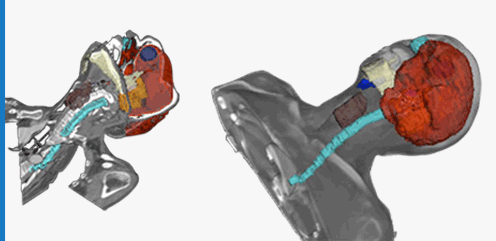

The Axellis system is used in the Treatment Center to capture 3D patient images for input to the

patented Axellis system with which users can design and manufacture tailored restraints and

medical supports for individual patients via the on-

The Axellis Patient Imaging System can be used to accurately monitor the patient in 3D throughout

a treatment period and from session to session, enabling treatment professionals to make informed

decisions regarding the efficacy of the treatment plan and helping to minimize interruptions to

treatment regimes .